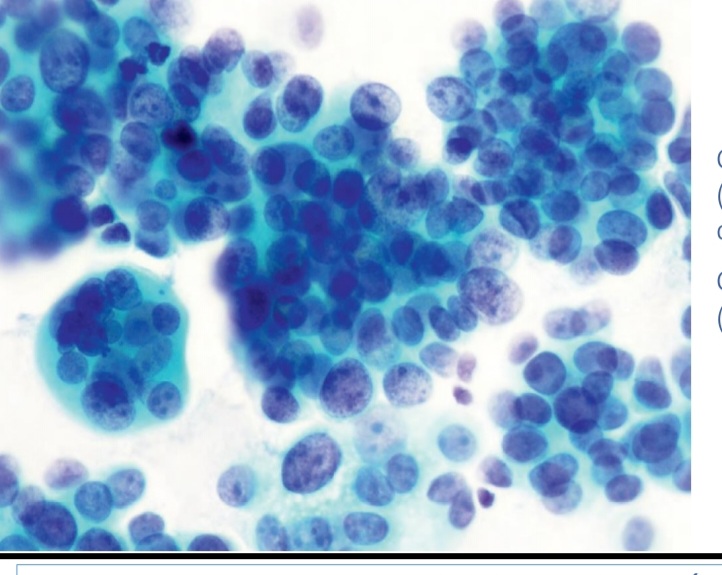

Artritis reumatoide ( ragocitos)